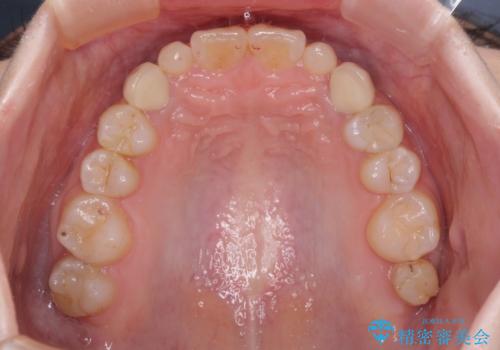

欠損と残存乳歯 矯正治療とインプラント治療

- 残存した乳歯や歯の欠損、歯並びを気にして来院された患者様です。

乳歯を残した状態は予後がよくないこと、矯正治療と補綴治療を総合的に進めていきたいとのことで、インビザラインによる矯正治療とインプラント補綴治療を並行して進めていくこととしました。

当院は矯正治療もインプラント補綴治療も、同一の歯科医師が担当するため、矯正治療を行いながら、最適なタイミングでインプラント補綴治療を行うことが可能です。

気になっていた部分がすべて解消され、患者様には大変満足していただきました。